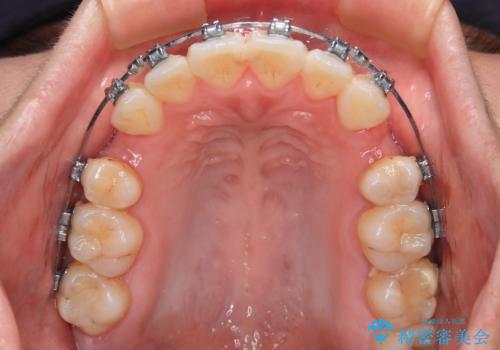

- 矯正装置

- メタルブラケット

- 治療期間

- 1年8ヶ月

舌突出癖の改善トレーニングは、仕上がり、治療期間、そして治療後の後戻りに大きな影響を及ぼします。

トレーニングをしっかりと行っていただいたため、スッキリとした口元に仕上がりました。